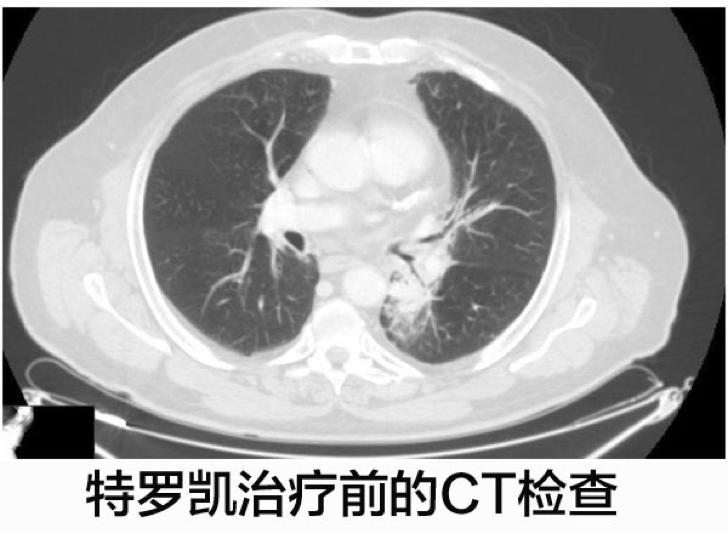

经过CT影像学扫描显示左肺有一个33毫米×33毫米的实性结节,胸膜和肺血管出现了浸润。经过CT引导的穿刺活检显示为EGFR基因野生型的腺癌,由于病人具有慢性阻塞性肺病,肺部病变的根治性手术被排除在外。

这名病人开始了厄洛替尼(特罗凯)的二线治疗,每天的计量是150mg,特罗凯治疗4个月之后CT显示肺部病灶体积减少。